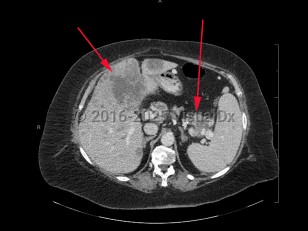

Metastatic pancreatic carcinoma

Pancreatic tumors arising from the head and neck of the pancreas (60%-70% of exocrine pancreatic cancers) may spread locally to the celiac axis or the peripancreatic and periportal areas. Pancreatic tumors arising from the tail of the pancreas (20%-25% of exocrine pancreatic cancers) may spread to the common hepatic artery, celiac axis, splenic hilum, or splenic artery. Patients with spread to the mesentery may present with ascites.